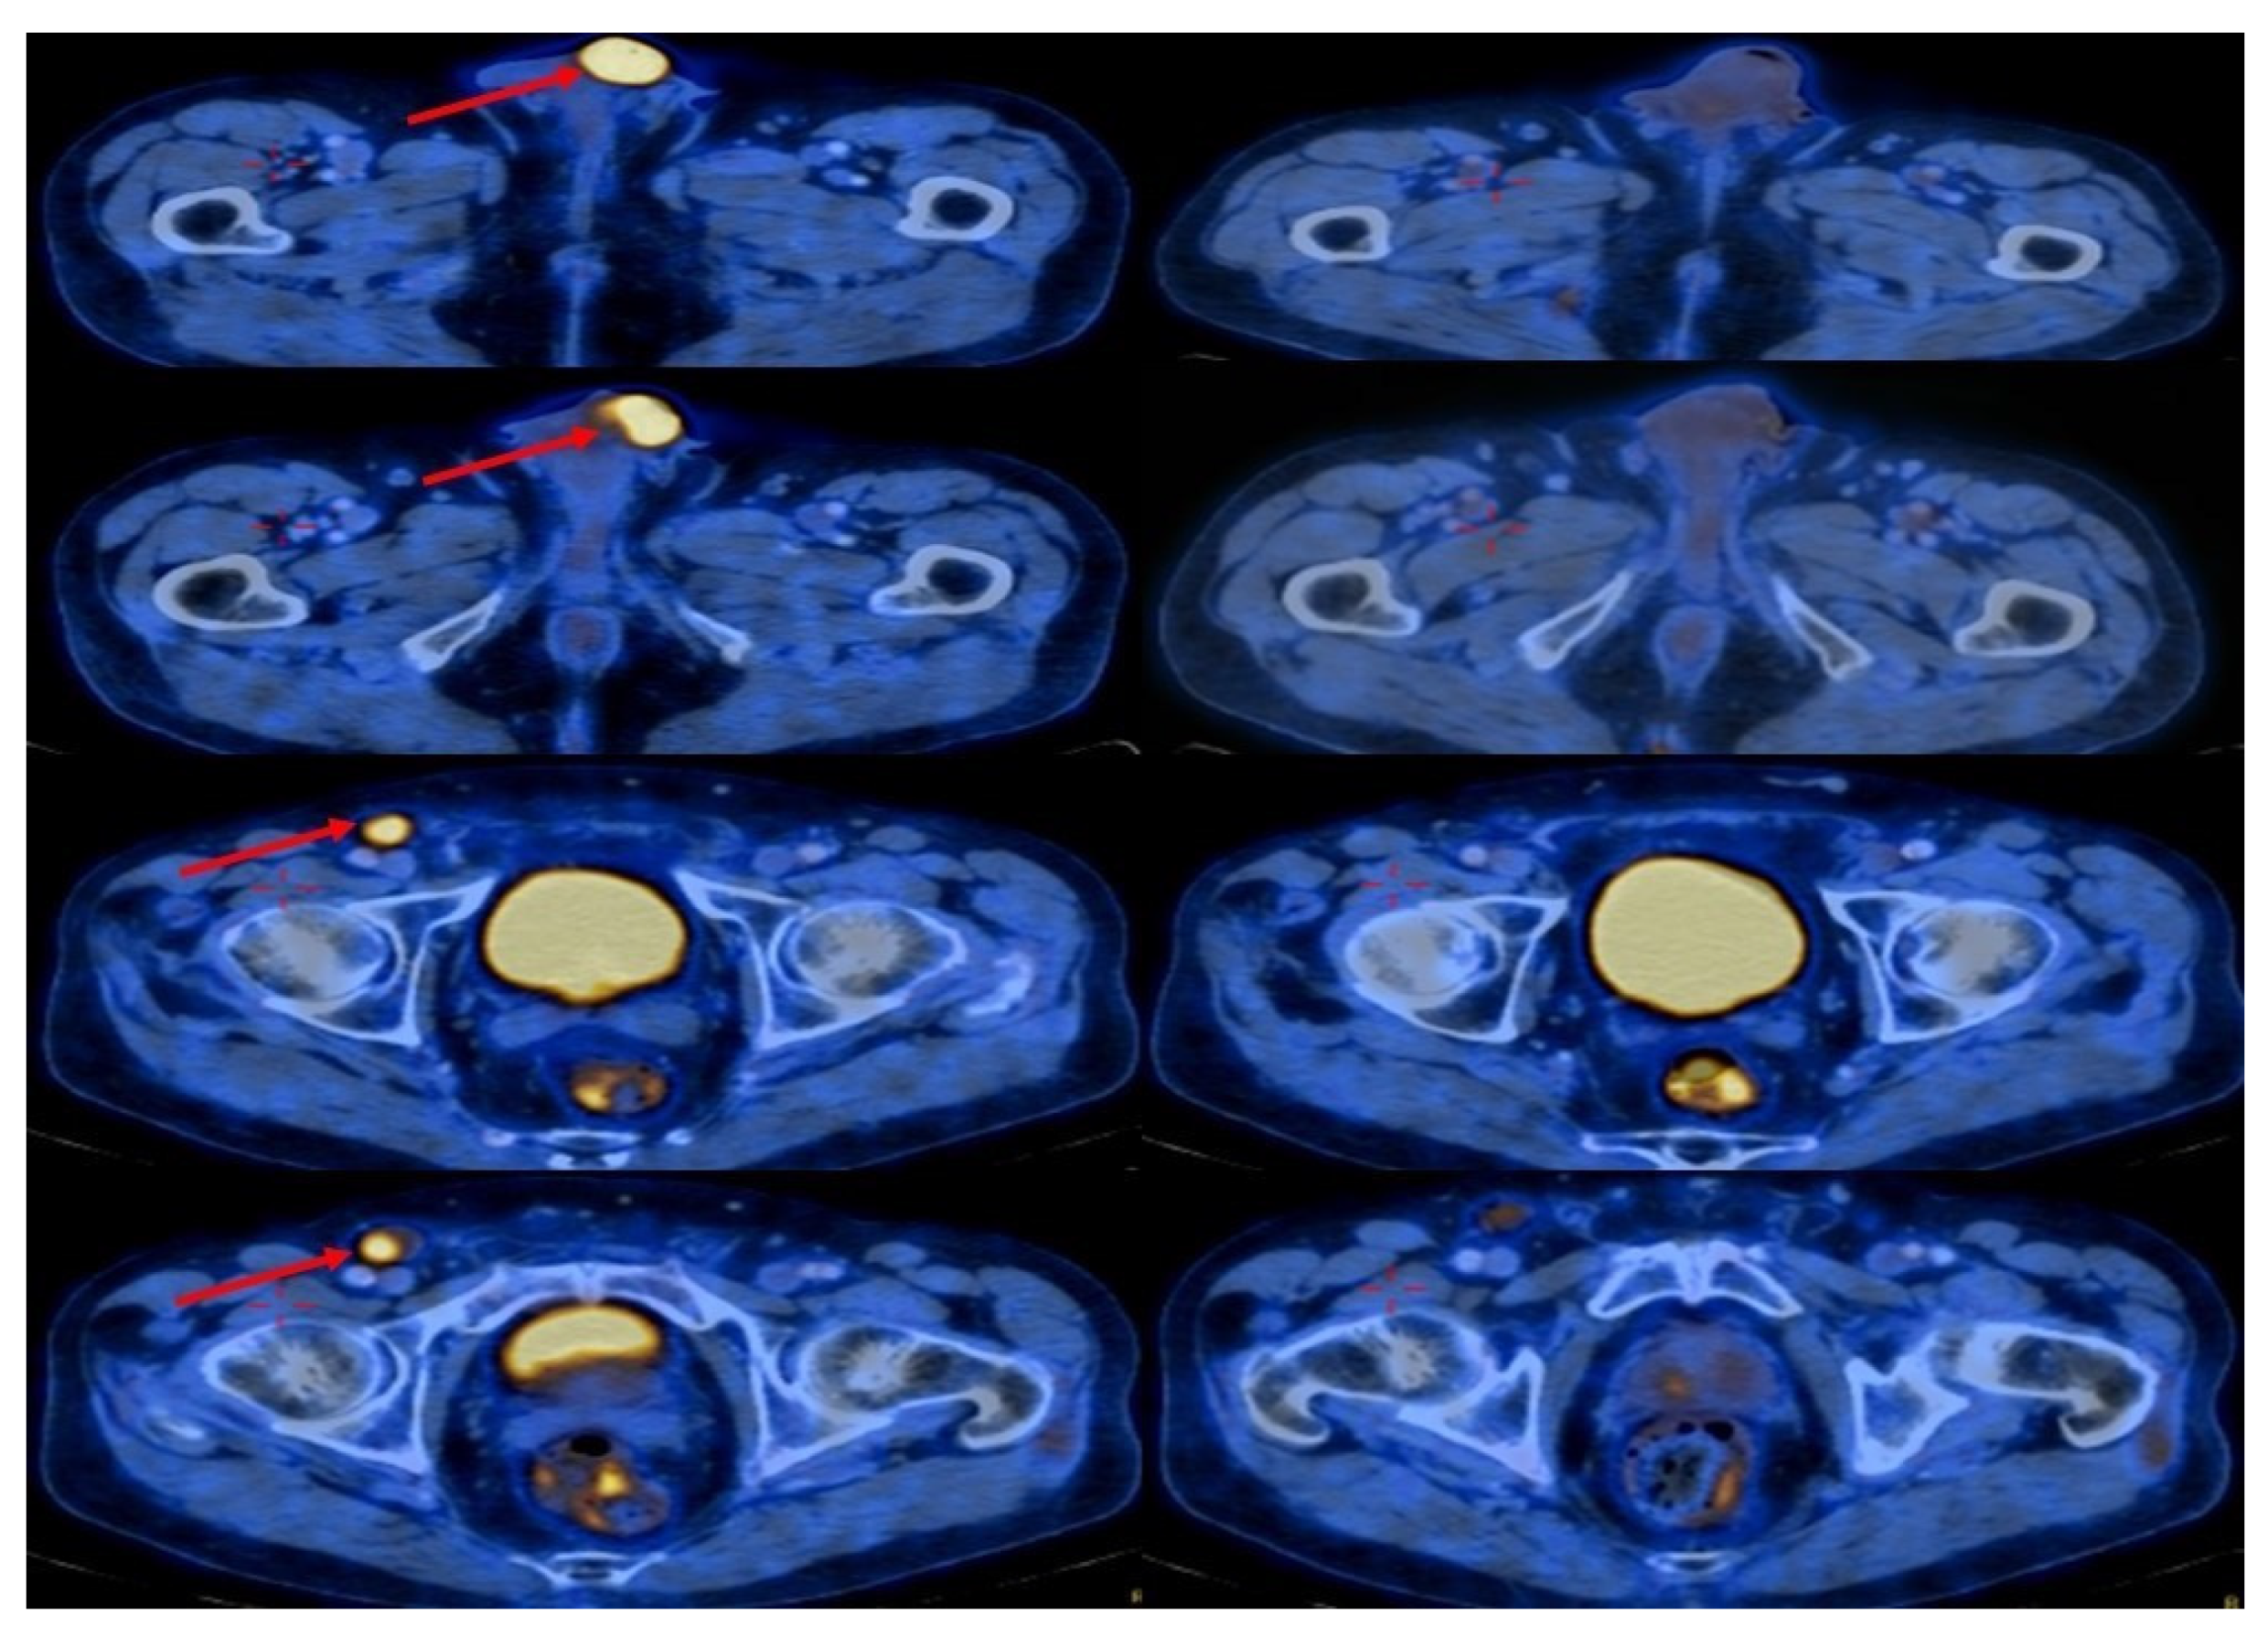

3.1. Elderly Patient with a Chronic Renal Failure

3.2. Eligible for Cisplatin but Refusing Surgery and Chemotherapy

3.3. Chronic Renal Failure with Extensive Disease